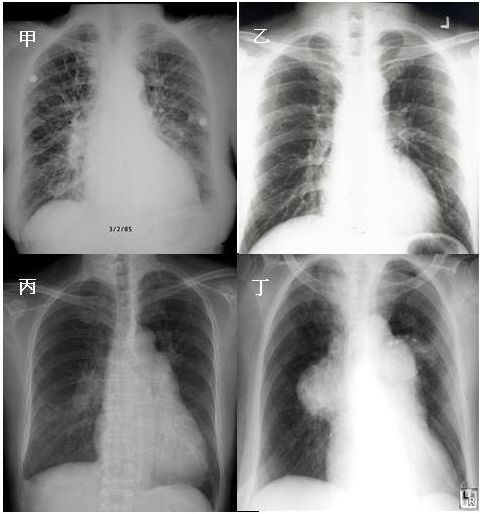

17. 60歲男性,患有糖尿病及肺氣腫,因嚴重社區型肺炎併發急性呼吸窘迫症候群及呼吸衰竭插管住進加護病房。住院十天後,情況逐漸穩定,但偶爾會躁動及咳嗽。體溫 37.5℃, 血壓 115/70 mmHg, 心速率 90/min, 規則, 呼吸速率 22/min, SaO2 94% (使用 Fi O2 70% , pressure control mode, PEEP 14 cm H2O, plateau pressure 34 cm H2O)。隔日早上護士小姐緊急通知病人突然意識喪失,四肢發紺,血壓60/30 mmHg , 心跳突然增快到150/min : 體溫38℃, 呼吸速率35/min, 呼吸音微弱,呼吸器呈現 high pressure alarm, 即使以ambu bagging 也很難將氧氣送入。此病人之休克最有可能是下列哪一種?

(A) 肺動脈栓塞併阻塞性休克。 (B) 心肌梗塞併心因性休克。 (C) 肺炎惡化併敗血性休克。 (D) 張力性氣胸併阻塞性休克。 (E) 心室上頻脈併心因性休克。